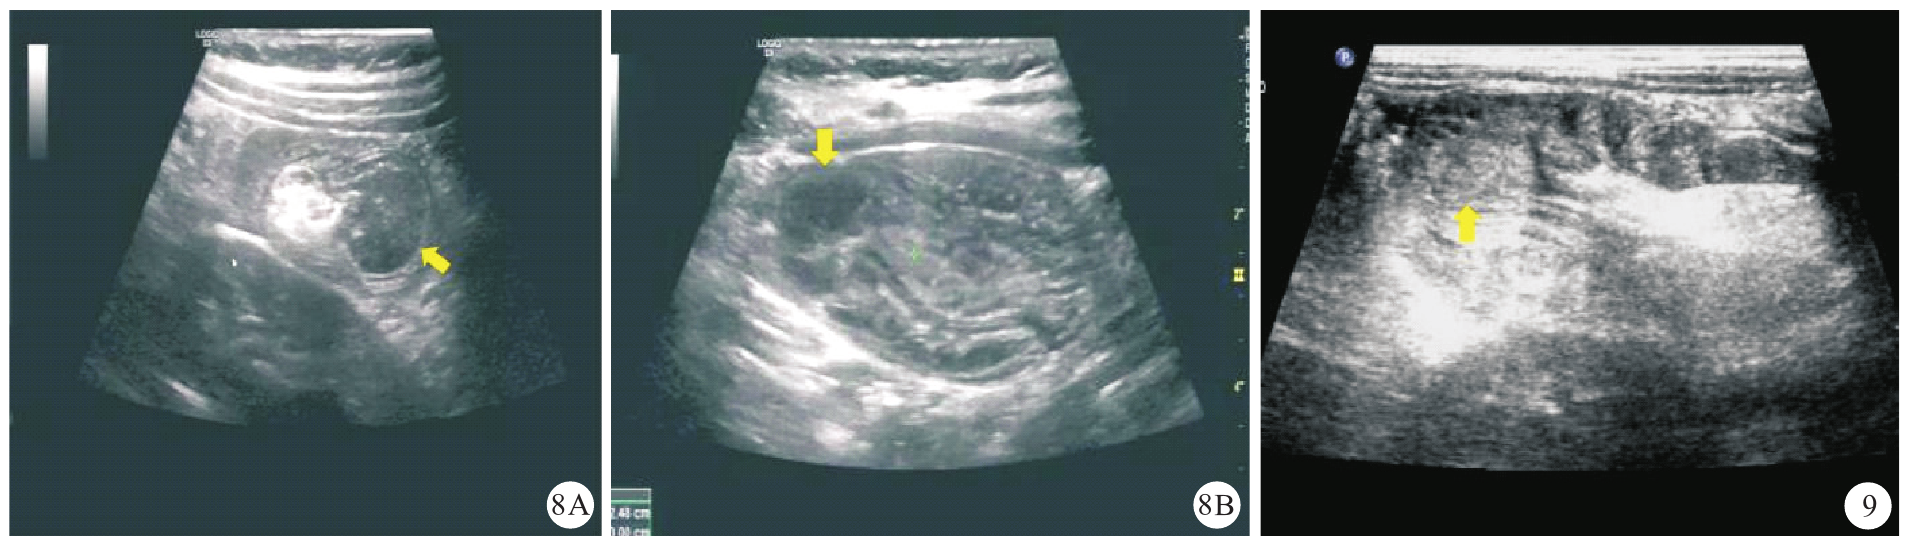

图7 本研究1例无PLP误诊为梅克尔憩室继发肠套叠患儿(男性,8个月龄)的超声声像图[图7A:纵断面套筒内可见水肿增厚的肠壁呈假性偏心厚壁肠袢(黄色箭头所示);图7B:横断面示套筒不伴大于3层的多重靶环征象]注:PLP为病理诱发点

图9 本研究1例海绵状血管瘤继发性肠套叠误诊为肠息肉继发性肠套叠患儿(男性,2岁4个月)的超声声像图(黄色箭头所示)]